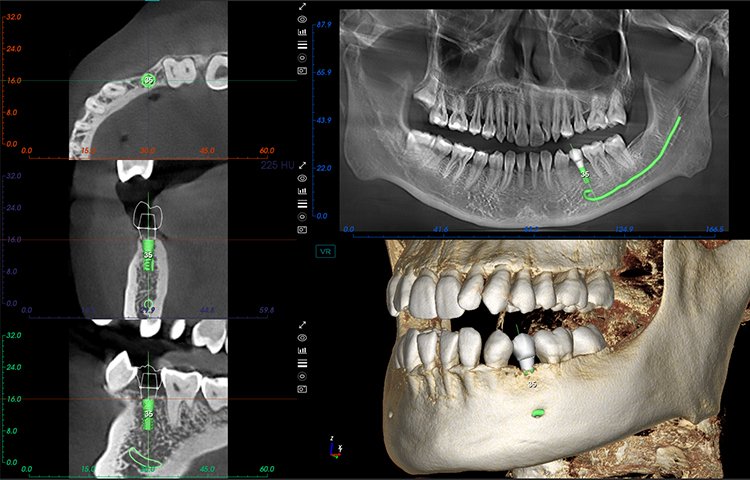

- Amplio campo de visión, satisfaciendo las necesidades clínicas generales.

- Potente funcionalidad, mejorando fácilmente la eficiencia clínica.

Potente Funcionalidad

El software de diagnóstico 3D líder de Meyer y el sistema de análisis ortodóntico inteligente adoptan un diseño de UI modular, lo que hace que las funciones del software sean más cercanas a las necesidades clínicas y más fáciles de usar para los médicos, reduciendo significativamente el costo de aprendizaje.

Software de Diagnóstico 3D

MyDentViewer